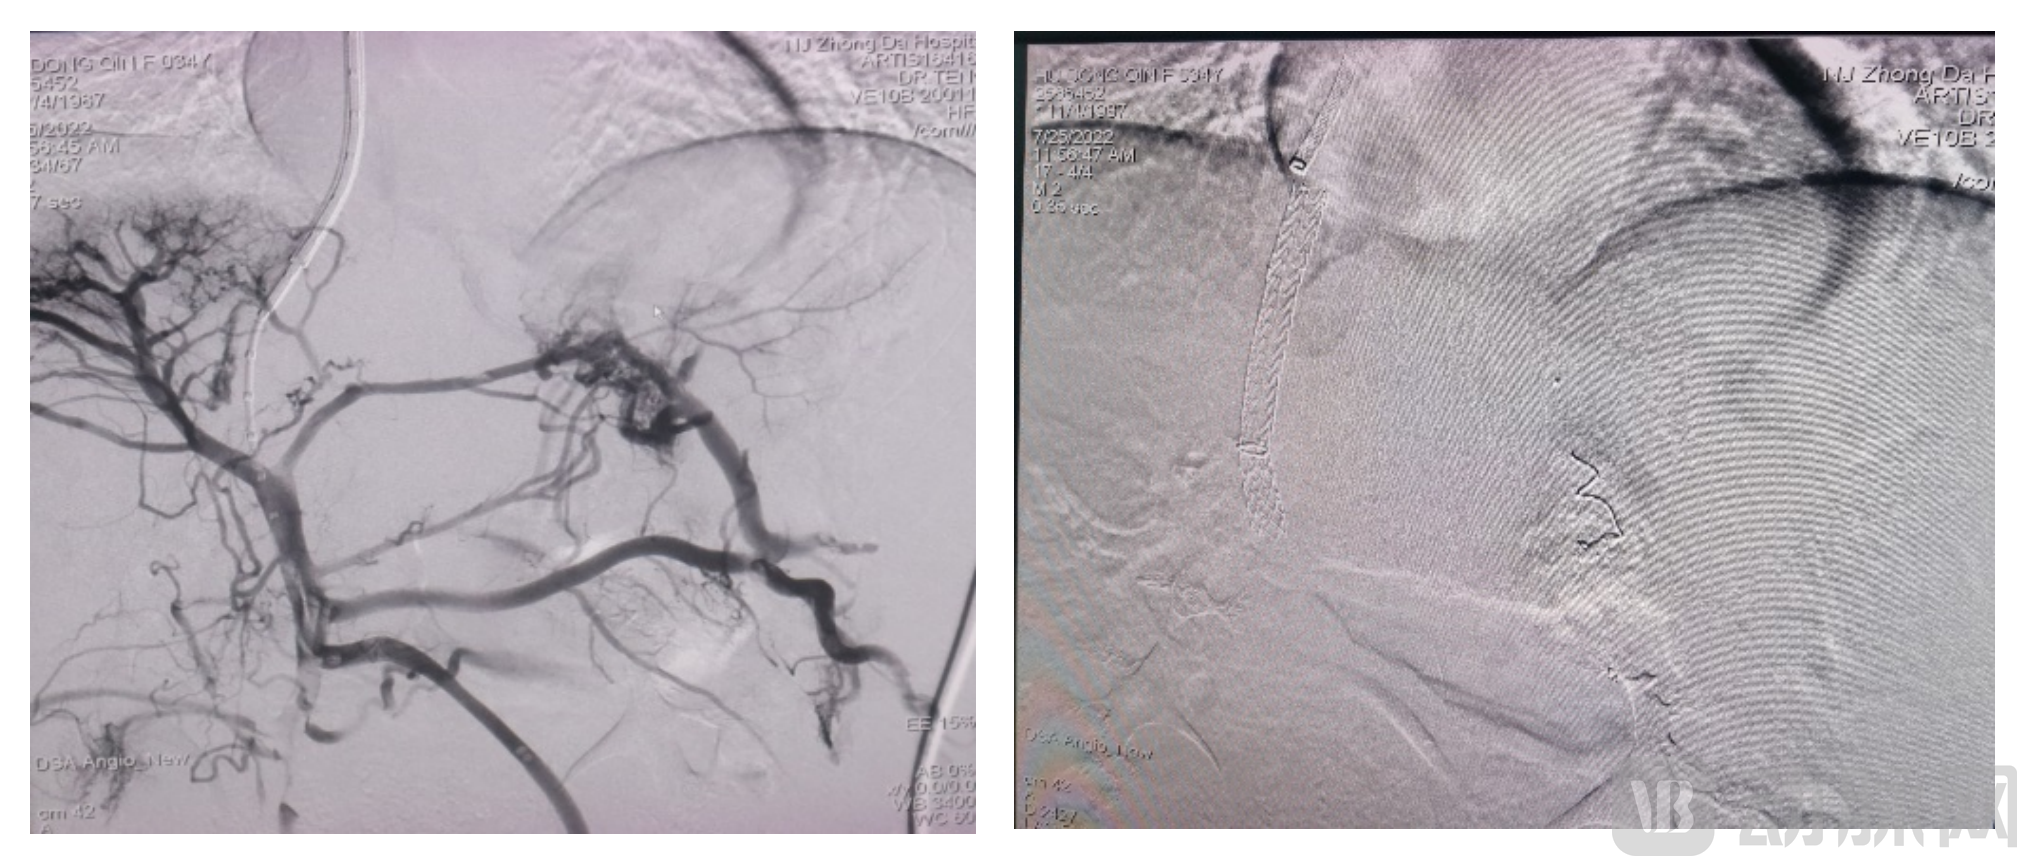

据介绍,首例临床受试患者为35岁女性,诊断为肝硬化、脾大、食管胃静脉曲张,门脉主干、左支和右支纤细,穿刺难度较大。在经过多次尝试,顺利完成穿刺之后,用6mm球囊预扩处理,植入一枚8mm×7cm支架,用8mm球囊后扩。支架输送和释放过程顺畅,形态完整、定位准确。患者门静脉压力由21mmHg降到9mmHg,成功达到分流效果。